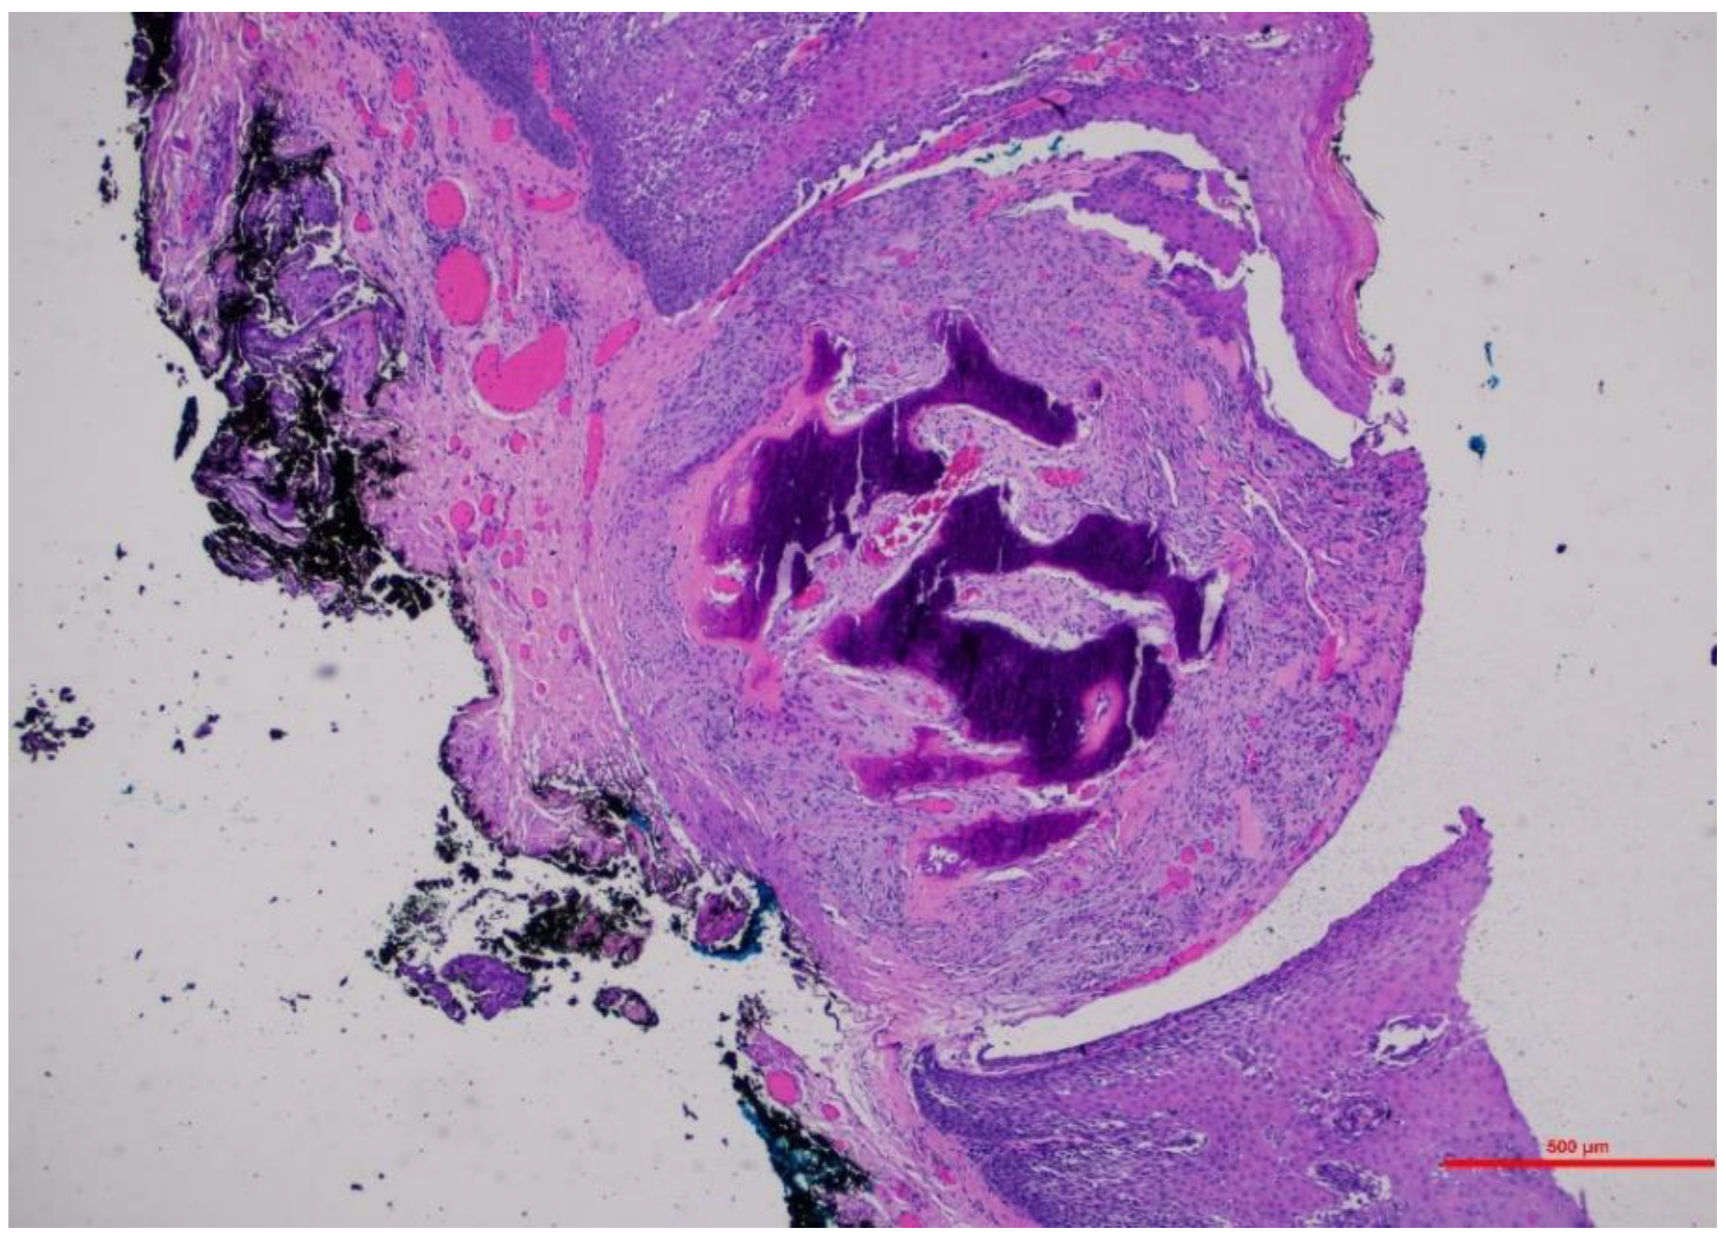

3.1.1. Case 1

3.1.2. Case 2